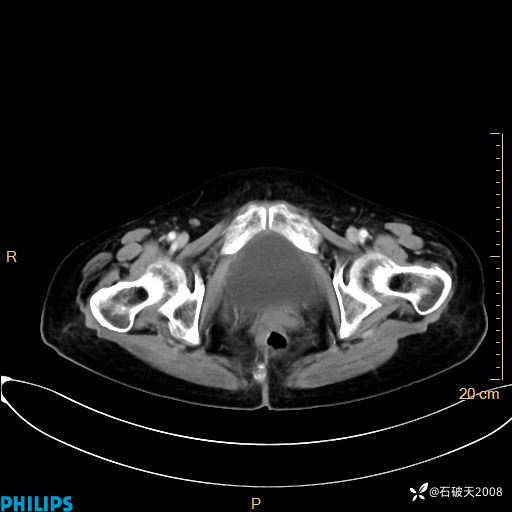

动脉期